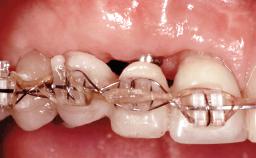

Replacement of Four Incisors with a Fixed Partial Denture on Two Narrow-Neck Implants after Implant Failure

| Loading Protocol | Conventional or early |

| Retention | Screw-retained, with splinted implants Screw-retained, with splinted implants |

| Provisional Implant-Supported Prosthesis | Prosthodontic margin >3 mm apical to mucosal crest Prosthodontic margin >3 mm apical to mucosal crest |

| Occlusion/Articulation | Harmonious |